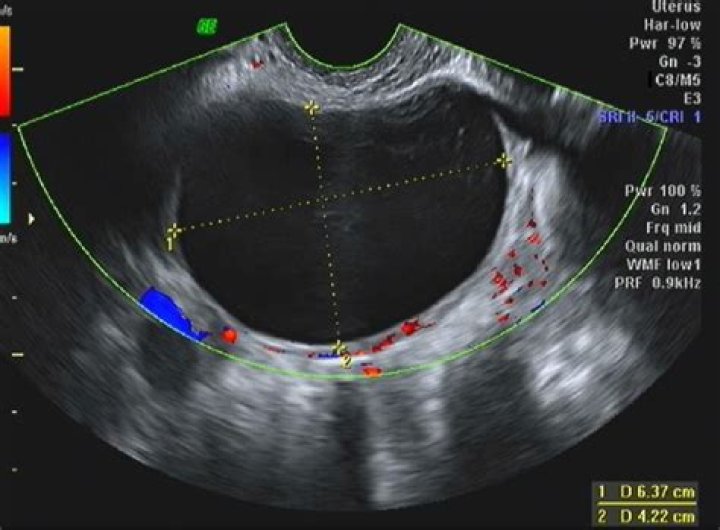

A simple cyst is a round or oval anechoic fluid collection with smooth thin walls, no solid component or septation, and no internal flow by using color Doppler imaging (Fig 1). When describing cysts in the pelvis, we use the term adnexal if the cyst is not clearly arising from the ovary.

What is considered a large adnexal mass?

If an adnexal mass larger than 6 cm is found on ultrasonography, or if findings persist longer than 12 weeks, referral to a gynecologist or gynecologic oncologist is indicated.

Is an adnexal mass a cyst?

Adnexal masses are characterized on ultrasonography as cystic, solid, or complex. According to an American College of Radiology guideline, simple cysts in premenopausal women are considered benign. 11 Complex masses may rarely be malignant in premenopausal women.